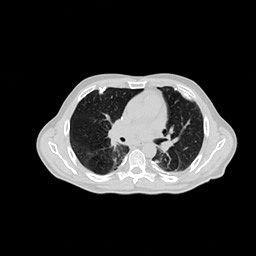

(a) Ground Truth

30.15dB

(b) ASD-POCS

39.35dB

(c) RBP-DIP

27.10dB

(d) DIP

23.88dB

(e) MED50

20.59dB

(f) RED-CNN

We have also conducted comparative analyses with pre-trained models MED50 and RED-CNN under multiple conditions. These models share similar network structures and complexities with the RBP-DIP framework. We have opted not to examine models with more complicated networks, as the proposed method is untrained, necessitating a focus on the structural properties of the networks for equitable comparisons. Theoretically, pre-trained models should outperform the proposed framework in most cases, especially when the number of measurements is not enough, as they can acquire extra information from training datasets. However, as shown in Fig.5 and Fig.6, RBP-DIP outperforms the two pre-trained models in most cases, with the only exception being limited-angle fan-beam reconstruction where the angular range is .

Pre-trained models’ low performances may be caused by the limited number of views. In the original research, the network inputs are high-quality FBP images (with 400 views), which possess sufficient projections and relatively minimal artifacts. In that case, the inconsistencies between the input and the corresponding output are relatively small, so that pre-trained models can learn the correct prior with limited training data. In our experiments, the FBP images always suffer from severe artifacts, and the aforementioned differences are relatively large. As a result, pre-trained models cannot be trained properly without a large, high-quality training dataset. In fact, some training instances in the current training dataset may even downgrade the performance of pre-trained models due to discrepancies in postures and CT slices, as illustrated in Fig.12.

Also, Fig.5 and Fig.6, particularly Fig.6b, show that an increasing number of views does not sufficiently lead to improved performance of pre-trained models. The reason is that pre-trained models aim to learn the mapping between the input and the corresponding output from training datasets, rather than actually solve the corresponding inverse problem. Increasing the number of views cannot directly strengthen this mapping. Conversely, the proposed RBP-DIP directly minimizes the inconsistency between the ground truth and reconstructed images under the same measurements. Increasing the number of views reduces the dimensions of the solution space and thus benefits both network optimization and the iterative reconstruction (IR) algorithms integrated in the RBP connection. This outcome is further verified in the last row of Fig.7, and Fig.8, where RBP-DIP considerably outperforms other methods.